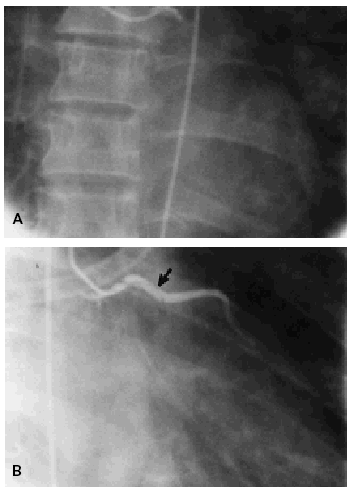

Una mujer de 45 años ingresó en la unidad coronaria de nuestro centro por presentar un dolor torácico de características anginosas de una hora de evolución. No tenía factores de riesgo cardiovascular, antecedentes de enfermedades reumatológicas ni ingesta de anticonceptivos, y tampoco antecedentes familiares de cardiopatía isquémica. A su llegada al servicio de urgencias se observó en el electrocardiograma una lesión subepicárdica desde V1 hasta V6 y en DI y aVL, que sugería un infarto agudo de miocardio anterior extenso. En la radiografía de tórax no se observaban datos de fallo cardíaco. Se realizó trombólisis con urocinasa (2 x 106 U administradas por vía intravenosa durante 10 min). Posteriormente, la paciente mejoró, desapareciendo el dolor torácico y persistiendo una menor elevación del segmento ST. Sin embargo, a las 48 h de su ingreso la enferma comenzó a presentar de nuevo dolor anginoso y cambios en el electrocardiograma, similares a los de su ingreso, acompañados de inestabilidad hemodinámica. Se realizó una coronariografía urgente, que demostró una oclusión del segmento distal del tronco de la arteria coronaria izquierda, provocada por una amplia disección que se extendía hacia la arteria descendente anterior (fig. 1). El resto del árbol coronario era liso y sin lesiones ateroscleróticas. En esta situación, la paciente fue sometida a una revascularización miocárdica mediante la implantación de un puente de safena a la arteria descendente anterior. Su evolución postoperatoria fue tórpida, falleciendo una semana después de la cirugía.

Figura 1. Proyección en oblicua anterior derecha en la que se observa una obstrucción en el tronco de la coronaria izquierda (A). Al rellenarse la arteria descendente anterior se aprecia una imagen típica de disección que se inicia en el tronco de la coronaria izquierda (B).